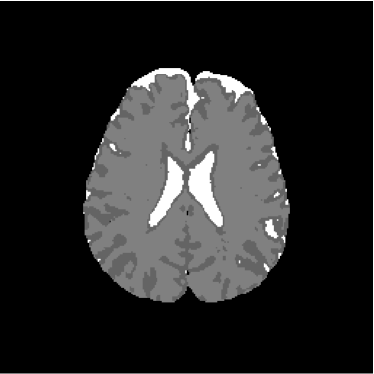

Figure 13 shows the training set mounted on the 13th slice of the volume of ADC maps. Figures 14 and 15 show the ground truth volume and the 13th slice, respectively.

Refer to caption

Figure 14: Ground truth image (13th slice) generated by polynomial net classification

Figure 28 shows 13th slice of classification result obtained by the use of the objective dialectical classifier. Figure 29 exhibits 13th slice of classification result after performing post-labeling, whilst figure 30 shows the entire volume generated by ODC classification.

The training process of ODC algorithm resulted in 6 classes. These classes were reduced to 4 after manual post-labeling, merging 3 classes out of brain region, namely image background, noise and cranial box. The post-labeling is manual because all 3 cited regions are statistically different and, consequently, they are merged due to our interest in classes more related to the brain regions. On figure 29 it is possible to notice that ODC was able to distinguish white matter from the gray matter present in the interface between liquor and white matter.